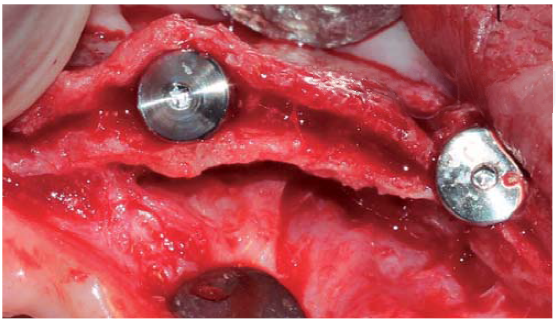

A full thickness incision over the crest was performed, raising a mucoperiosteal flap exposing bone table up to 4 mm from the top of the crest in vestibular direction; from that point the flap was divided into partial thickness (Figure 3). After this, impact points were marked in designated places according to surgical guide for implant placement; perforations were initiated with a 1.6 mm diameter burr in order to determine desired implant depth and axis. After this, a ridge was created on the crest with a diamond burr, fracturing cortical bone to create chisel's access to cancellous bone, and with the aforementioned, bone tables were separated until reaching a 5 mm depth (Figures 4 y 5). Perforations were further continued with a 2.0 diameter burr (Figure 6), and vestibular table expansion was undertaken creating greenstick fracture with the expanders, until reaching sufficient osseous bed diameter (3.2 mm diameter) (Figures 7 y 8). Implants were then placed at a 25 rpm speed and 35 Nem torque (Figures 9 y 10). After this, a particulate bovine bone graft was placed (Bonefill® Bionnovation Biomedical, Sao Paulo, Brazil) with the aim of preserving integrity of vestibular bone tables (Figure 11). All these procedures were repeated for placement of all six implants. Finally, sutures were undertaken with monofilament nylon 5/0.

For this surgical procedure, the patient received the same pre-surgical preparation than that used for the upper jaw. Procedure was initiated with an incision between grooves at the level of all teeth, after which a mucoperiosteal flap was raised. Teeth were then extracted and adjacent granulation tissue was removed, trying to preserve all bone remnants. After this, bone ridge was regularized and remodeled using multi-laminated burrs with abundant irrigation. With a conventional burr sequence, perforations were then initiated at places designed for implant placement. After this, all four implants were placed, locating prosthetic platforms at one same level. Since there was presence of bone defects and three walls around the implants, particulate bovine bone graft was placed (Bonefill® (R) Bionnovation Biomedical, Sao Paulo, Brazil). Finally, sutures were applied with monofilament nylon 5/0.

After six months, radiographic evaluation was conducted, which revealed preserved bone tissue surrounding the implants and no signs of complications. After this, surgical exposition and healing screw placement was undertaken and bone integration of all implants was observed.